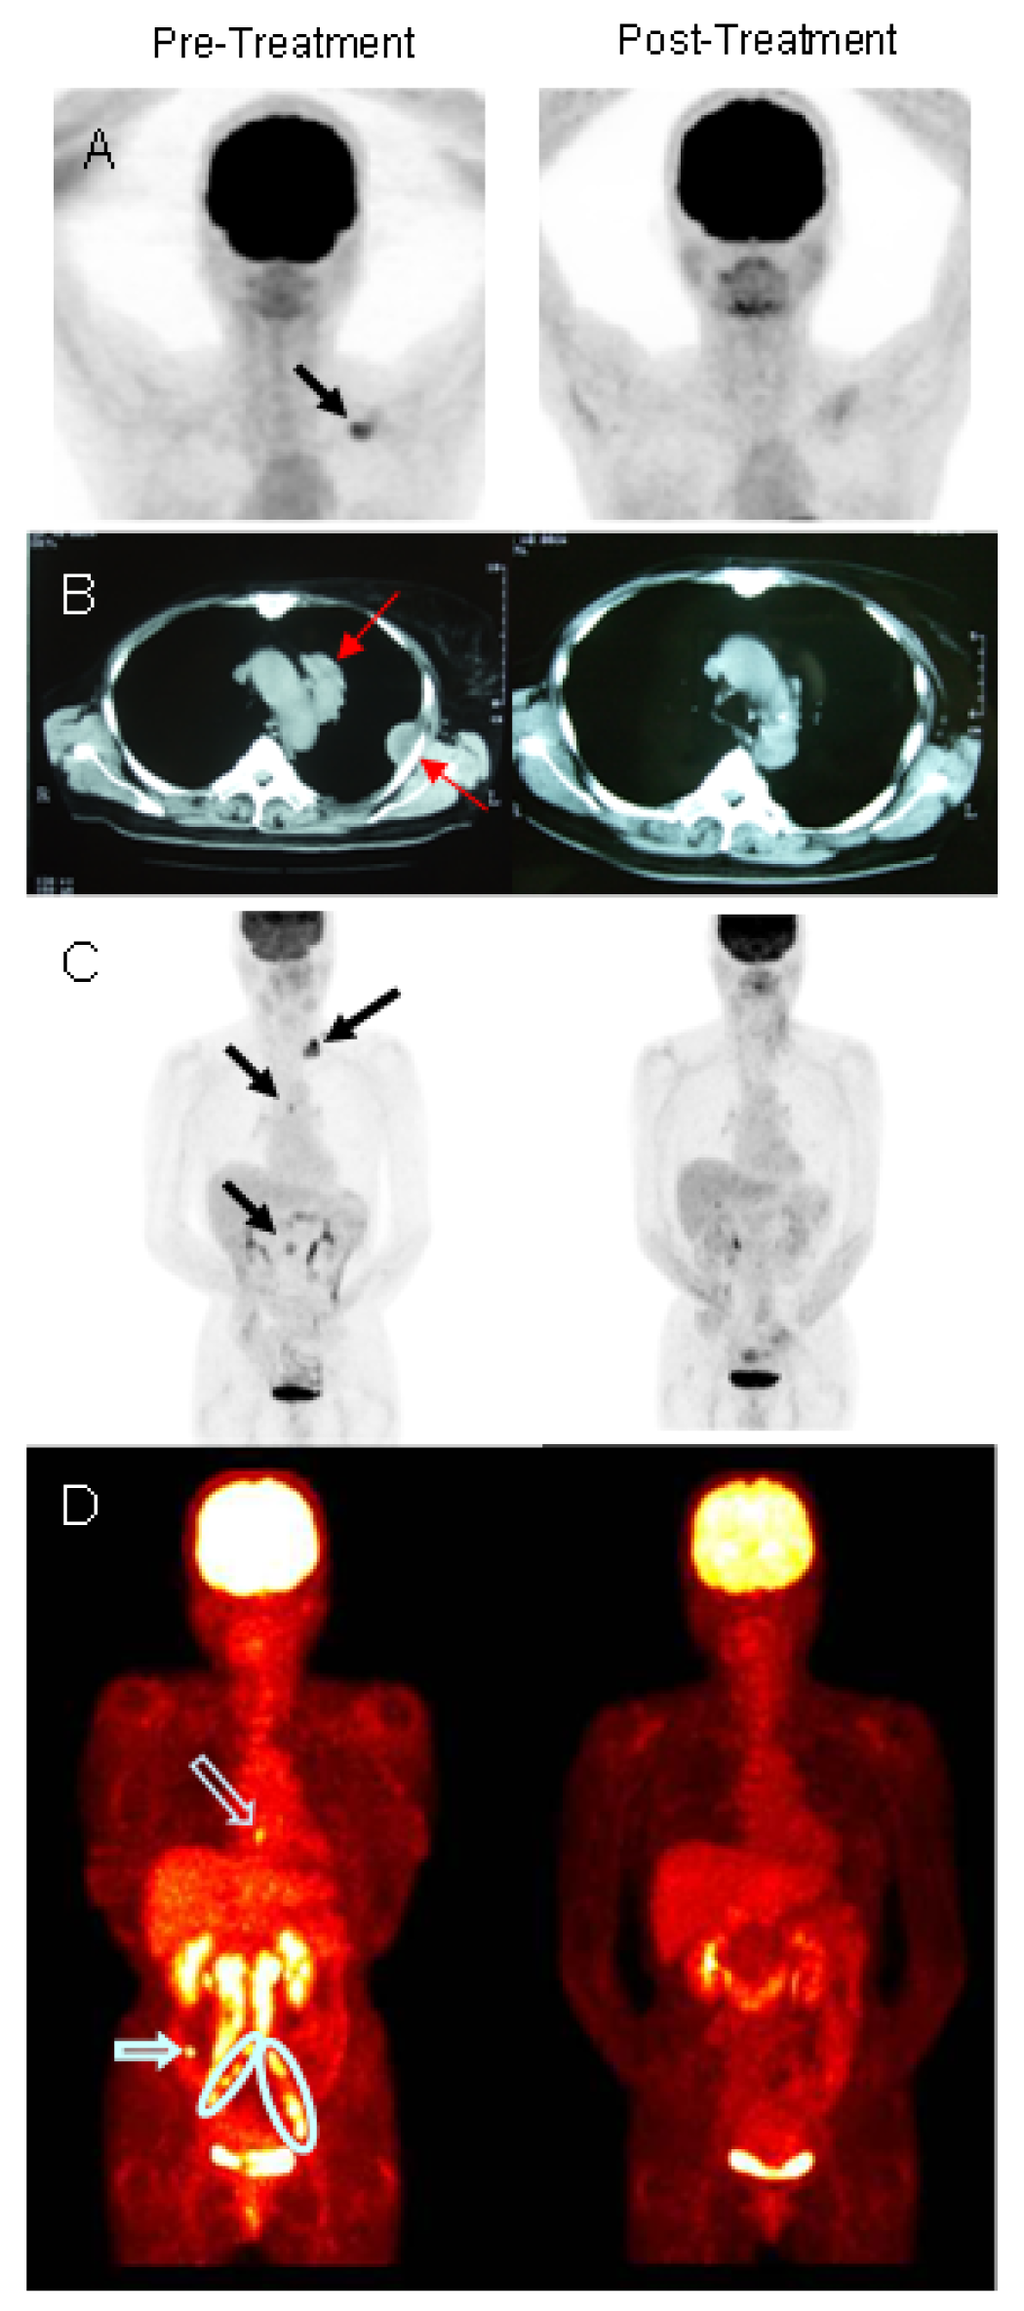

Examples of radiographic evidence of response to treatment are illustrated in Figure 2. Panel A shows the pre- and post-treatment CT of a breast cancer patient with metastatic disease confined to the supraclavicular region, probably lymph nodes. Another breast cancer patient had a complete response when treated for metastatic breast cancer involving the mediastinum and the chest wall (Figure 2B). The radiographic images of a patient with stomach cancer (Figure 2C) illustrate multiple metastatic lesions in the supraclavicular region, mediastinum, and periaortic lymph nodes at enrollment that completely responded to treatment. Figure 2D illustrates resolution of metastatic tumors at sites distant from the areas receiving iDC injection and IMRT in a patient with cervical cancer.

There were two components of the protocol that have therapeutic potential; that is, the immunologic response to the tumor and the effect of radiation. It is difficult, perhaps even impossible, to ascribe the responses observed to one or the other component. There are, however, several lines of evidence that we feel support our hypothesis that the combination employed is complimentary. The most robust argument is illustrated by the PET-CT shown in Figure 2D that clearly demonstrates the regression of metastatic lesions that were not subjected to either radiation or direct injection with iDC after such treatment of other lesions. Similar responses were seen in other patients.